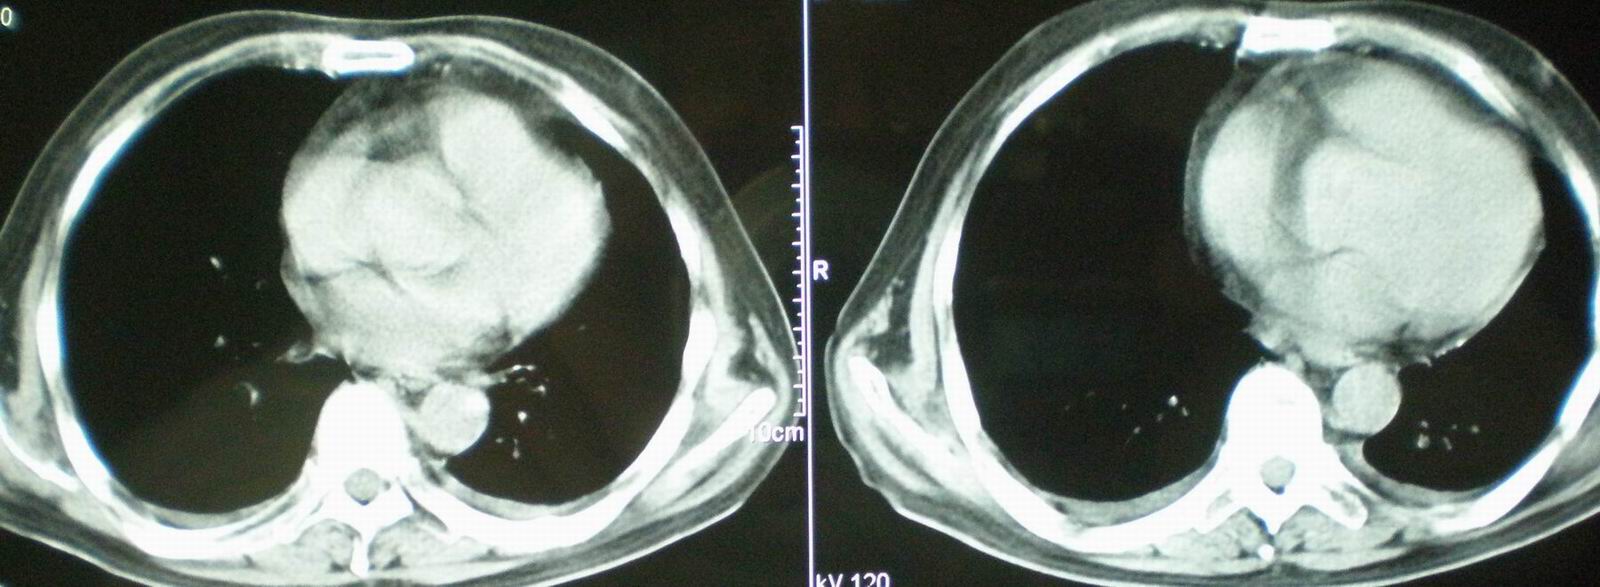

2008年11月18日今天的ct片

2008年9月18日ct片

[face=宋体]显然上级医院进行了抗结核,抗真菌,抗炎等治疗,目前病人肺内病灶基本消失,双侧胸腔积液,右侧积液量有吸收,抗结核一个多月,现在病人疑问,结核的诊断是否有疑义,抗结核是否继续,因为那个毕竟副作用大。[/face]

急性心衰所致肺水肿,双侧胸腔积液,少量心包积液可能?结合临床及其它检查.

我仔细看了下病人的出院小结,当时情况危急,诊断里有1型呼衰。心包周围的是脂肪密度。结合三次ct扫描的图象分析,个人认为:1、病人目前肺部病灶基本消失,双侧胸腔内少量积液,抗结核治疗才一个多月,就算是结核,抗结核治疗有效果,为何效果如此好,一点纤维灶的痕迹都没有呢,再就是患者做过气管镜检查及活检、痰检均未找到结核的证据。所以不支持结核的诊断。

2、结合现在的ct片,考虑:肺水肿及真菌感染,双侧胸腔积液。